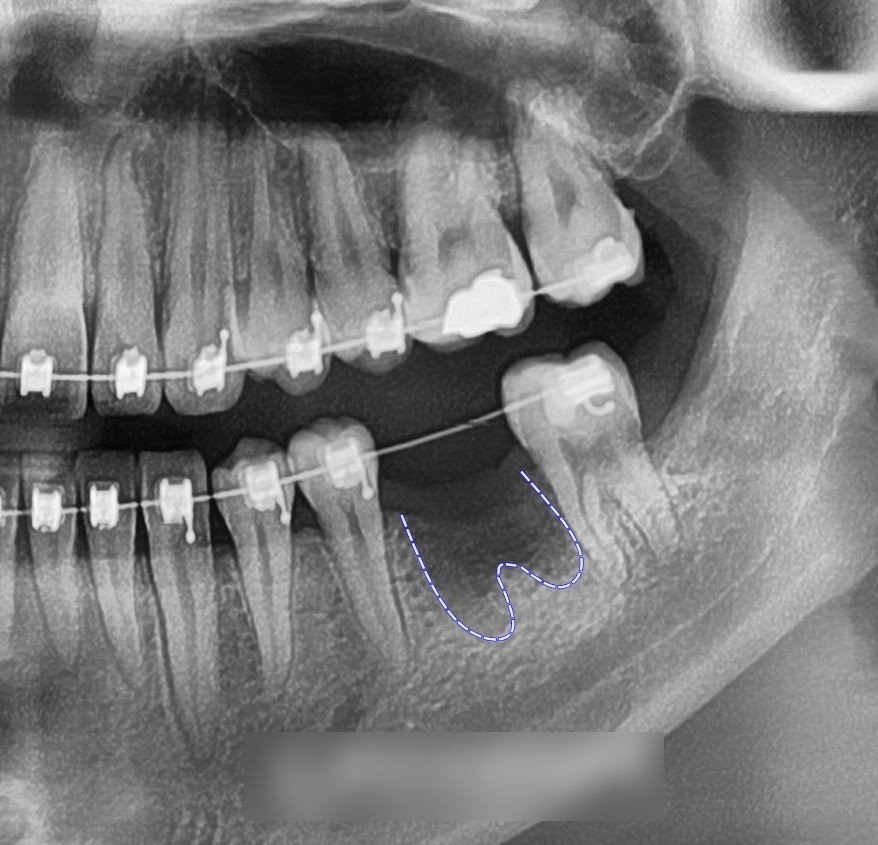

엑스레이를 통해 부러진 어금니의

잔존 치질이 거의 없는 상태라는 점도 확인되었고,

보존치료가 어려워 발치가 필요한 것으로

판단되었습니다.

촬영일 : 24.04.25

우선 남아있는 치근만 남은 어금니(#36)는

발치 후 치유 기간을 거쳤고,

그 사이 인접 치아들이 공간 쪽으로

쓰러지는 것을 예방하기 위해

공간 유지를 진행했습니다.

촬영일 : 24.04.25

이후 브라켓과 와이어를 이용해

인접치를 서서히 이동시킵니다.

촬영일 : 24.09.10/ 25.01.03

덧니를 해소하고 정중선을 맞추는 동시에,

임플란트 를 식립할 수 있도록

공간을 유지합니다.

교정 종료 시점에서는

어금니 부위에 임플란트 를 심어진 모습입니다.